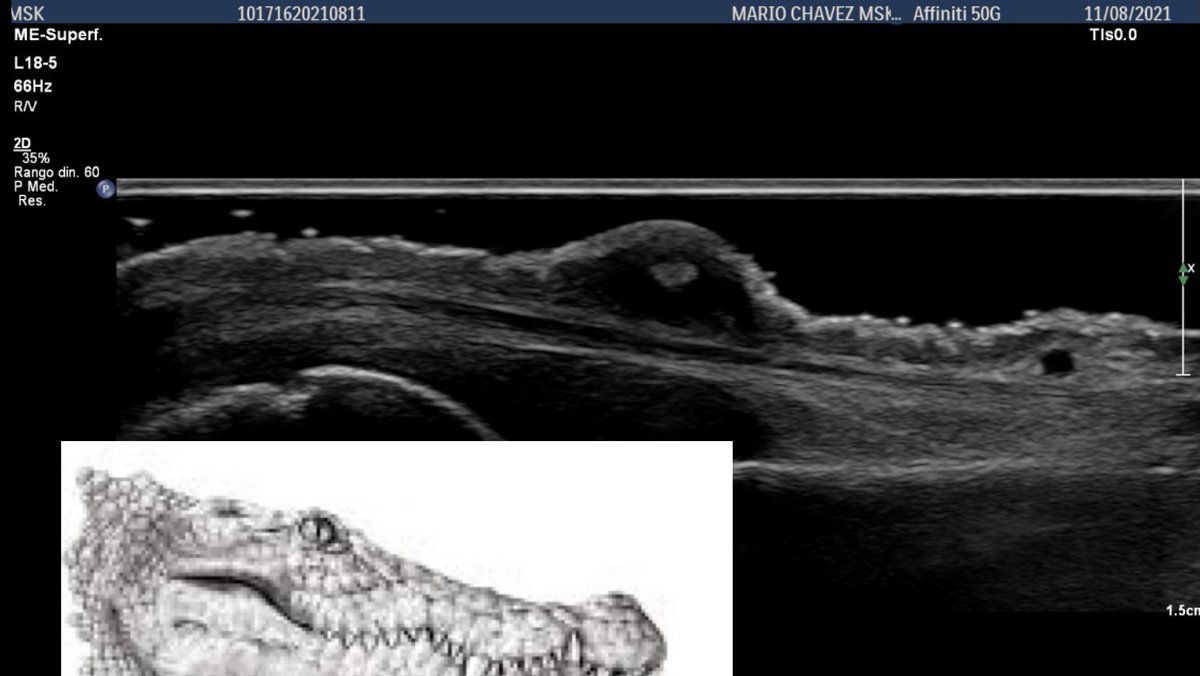

Crocodile 🐊 !!! 👀👀😮 William Morrison, MD Javier Merayo-Chalico Diana_reumatika Cristina Macía Philips POCUS MSK ULTRASOUND MASTERMIND® Ecografía en Reumatología 𝙳𝚛𝚊. 𝙰𝚗𝚊 𝙻𝚊𝚞 🇲🇽 CRUS-SURC Dr. Mendoza Torres Sᴡɪss Uʟᴛʀᴀsᴏᴜɴᴅ Cᴇɴᴛᴇʀ - UZR MGH Rheumatology MSK Ultrasound Program Gonzalo Serrano-Belmar. Abdulwahed AL zaher The Ultrasound Site - MSK ultrasound training Arthur Mandelin, MD/PhD, RhMSUS, RMSK João Freitas, MD MSK Australia Luis C. Rodriguez RheuMsk